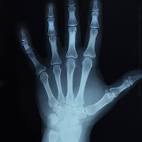

الأولى باستخدام الأشعة

http://t1.gstatic.com/images?q=tbn:A...UC5RDqkOa3L8aw

فتكون العظام الهشة ناصعة البياض و thinner

و لكن هذه الطريقة قد تكون غير دقيقة